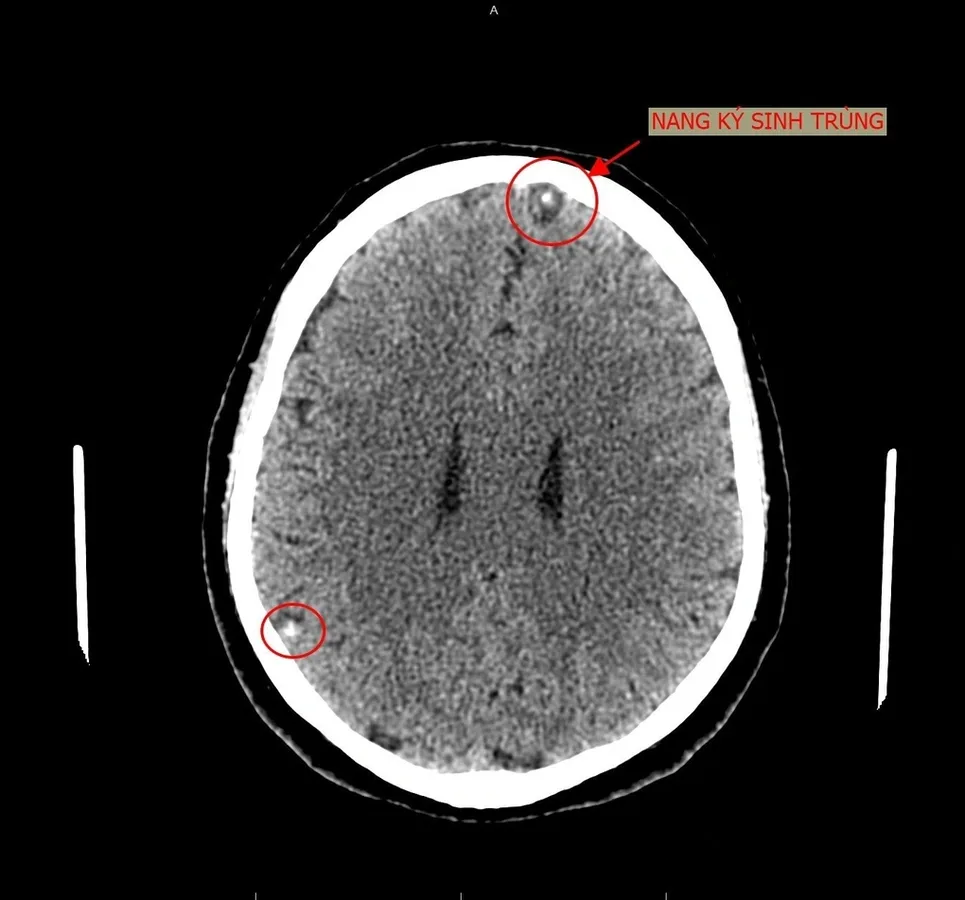

- Não: Ấu trùng sán lợn hoặc giun đũa chó mèo có thể di cư lên não, tạo thành các nang sán gây co giật, liệt nửa người hoặc mù lòa.